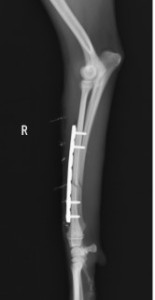

手術前 手術後

ロッキングプレートで整復しました。